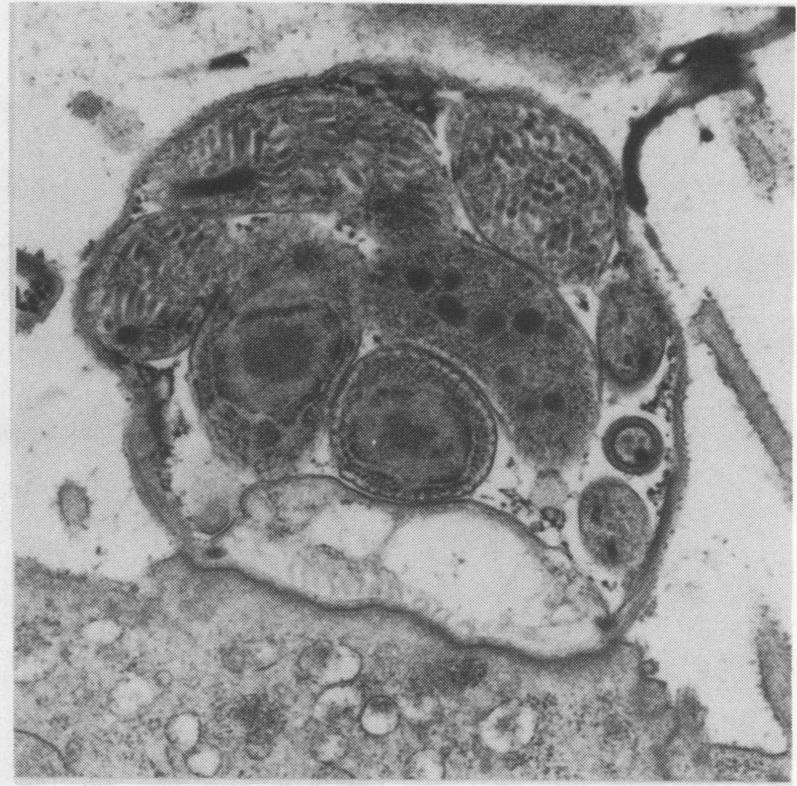

Opportunistic protozoan infections in human immunodeficiency virus disease: review highlighting diagnostic and therapeutic aspects.

摘要